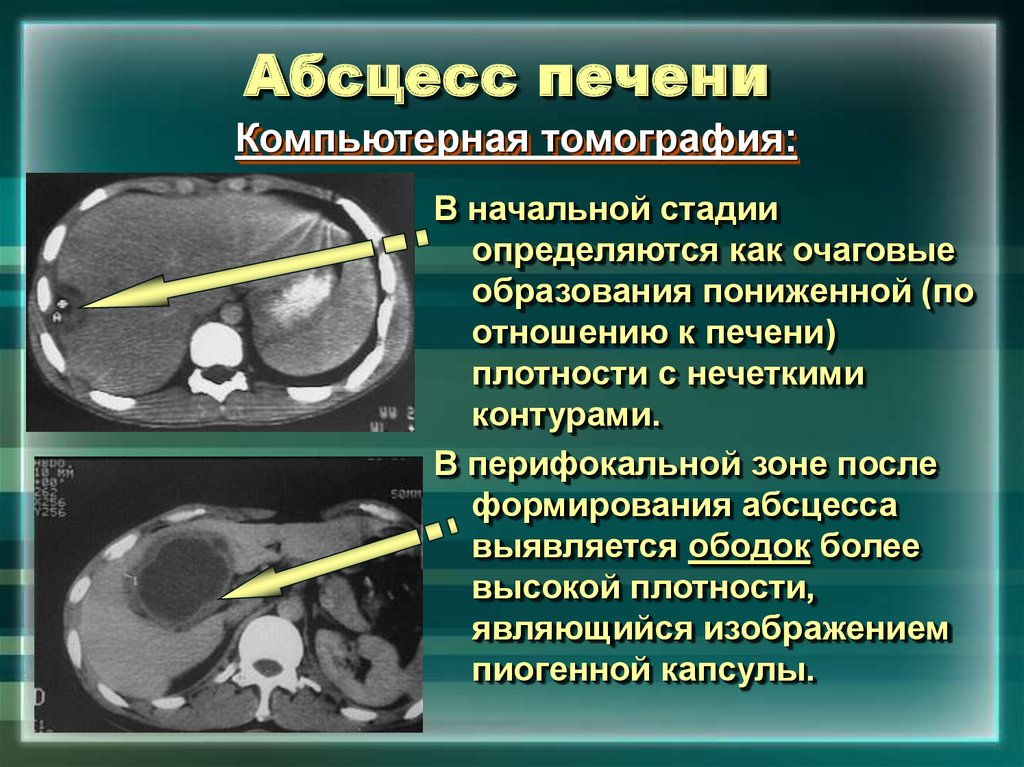

Онкология головного мозга. Раковые заболевания головного мозга. Амебиазный абсцесс печени. Солитарный абсцесс печени. Амебный абсцесс печени кт.

Амебиазный абсцесс печени. Солитарный абсцесс печени. Амебный абсцесс печени кт. Злокачественные опухоли щитовидной железы классификация. К злокачественным новообразованиям щитовидной железы относятся:. Доброкачественные щитовидной железы классификация. Доброкачественные новообразования щитовидной железы.